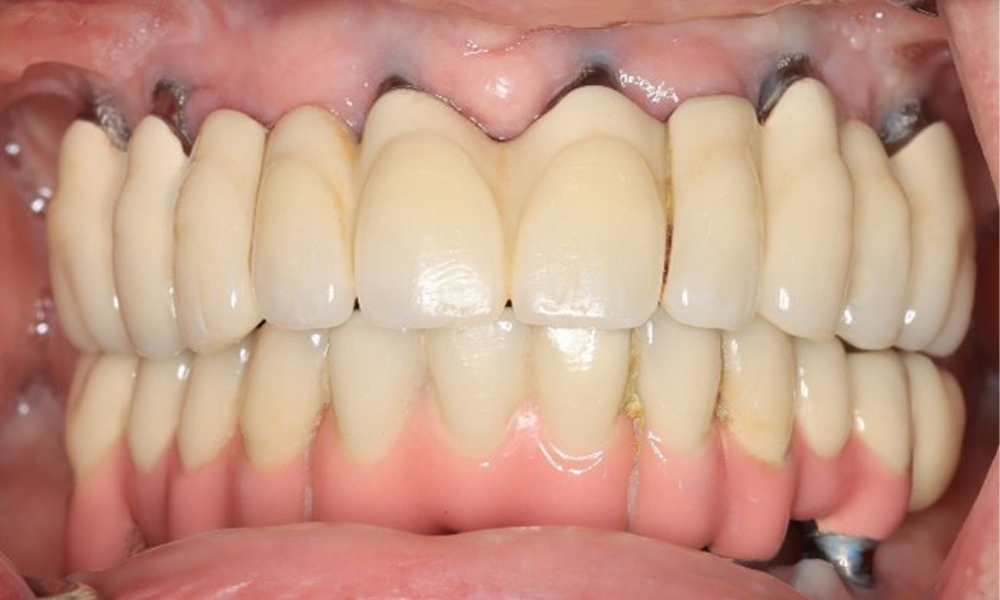

Преден изглед на зъбите (горна и долна челюст)

Фигура 3: Фронтален изглед

74-годишен пациент се явява за консултация. Анамнезата показва, че пациентът има добре контролирана хипертония и приема Lixiana. Освен това пациентът е имал карцином на бъбрека през 2020 г. Начинът на живот на пациента е без забележки. Няма останали естествени зъби и има шест импланта в горната и долната челюст, на които са поставени коронки или мостове. Текущите данни не показват периимплантатен мукозит или периимплантит, но въпреки това периодично има (незначително) кръвене при имплантите (възстановяванията).